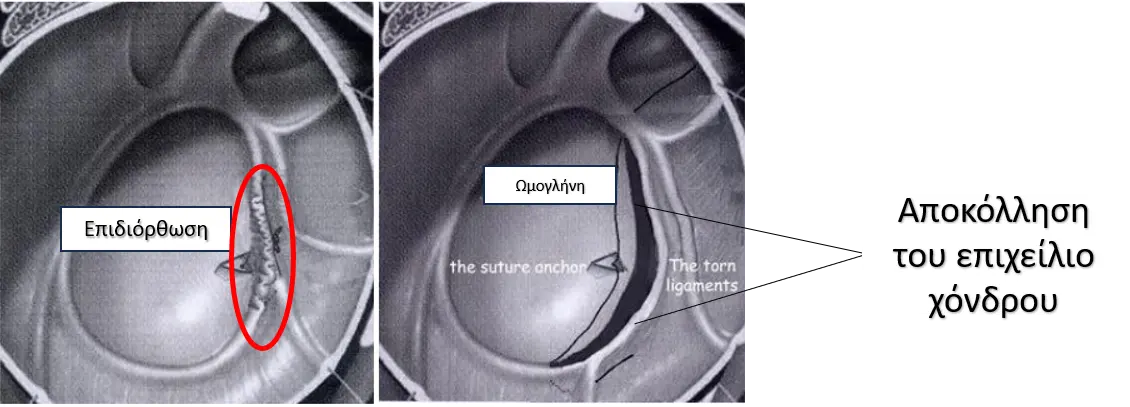

Τόσο το πρόσθιο όσο και το οπίσθιο χείλος της ωμογλήνης καλύπτονται από επιχείλιο χόνδρο. Πρόκειται στην ουσία για έναν συνδετικό ιστό που ενισχύει την σταθερότητα του ώμου. Όταν συμβεί ένα πρόσθιο εξάρθρημα ο επιχείλιος χόνδρος θα υποστεί είτε απλή ρήξη (βλάβη Bankart) είτε θα προκληθεί ένα οστικό κάταγμα στην ωμογλήνη (οστική Bankart). Επιπλέον, η κεφαλή του βραχιονίου μπορεί να υποστεί ένα εμπιεστικό κάταγμα στο ανώτερο και οπίσθιο μέρος της (βλάβη Hill Sachs). Τέλος, σε μεγαλύτερες ηλικίες το εξάρθρημα του ώμου μπορεί να οδηγήσει σε ποσοστό έως και 60% σε ρήξη των τενόντων του στροφικού πετάλου του ώμου.

Η επέμβαση πραγματοποιείται υπό γενική αναισθησία και νευρικό αποκλεισμό (μπλοκ). Μετά το χειρουργείο ο ασθενής θα παραμείνει στο νοσοκομείο για λίγες ώρες έως ένα βράδυ, εφόσον το επιθυμεί. Πριν το εξιτήριο θα σας δοθούν σαφείς οδηγίες για τις ασκήσεις που θα πρέπει να κάνετε, καθώς και περεταίρω συμβουλές για να σας καθοδηγήσουν στην ανάρρωσή σας. Η επιδιόρθωση γίνεται αρθροσκοπικά μέσω δύο ή τριών μικρών οπών μεγέθους 5 χιλιοστών. Στόχος είναι η επανακαθήλωση του επιχείλιου χόνδρου και των συνδέσμων που έχουν υποστεί ρήξη ή διάταση πίσω στην περιφέρεια της ωμογλήνης. Αυτό επιτυγχάνεται με την χρήση μικροσκοπικών βίο-απορροφήσιμων αγκυρών με ράμματα.

Σε ορισμένες περιπτώσεις και λόγω αυξημένης πολυπλοκότητα, μπορεί να χρειαστεί να πραγματοποιηθεί ανοικτή επιδιόρθωση των συνδέσμων ή ενίσχυση με οστικό μόσχευμα (Σπάνια – λιγότερο από 2%).